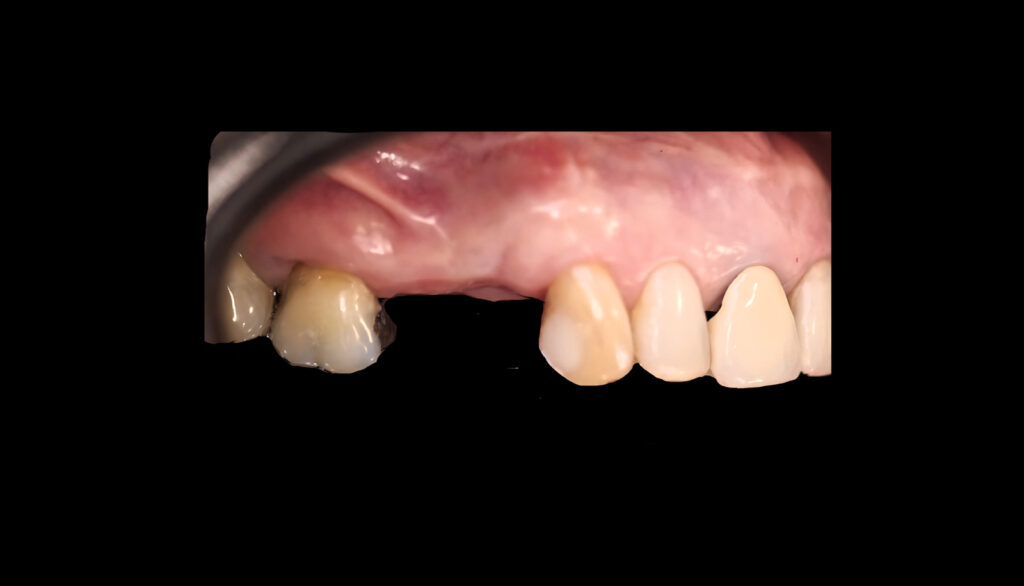

Zona 1.4 y 1.5

- Exodoncia + preservación alveolar

- Provisionalización